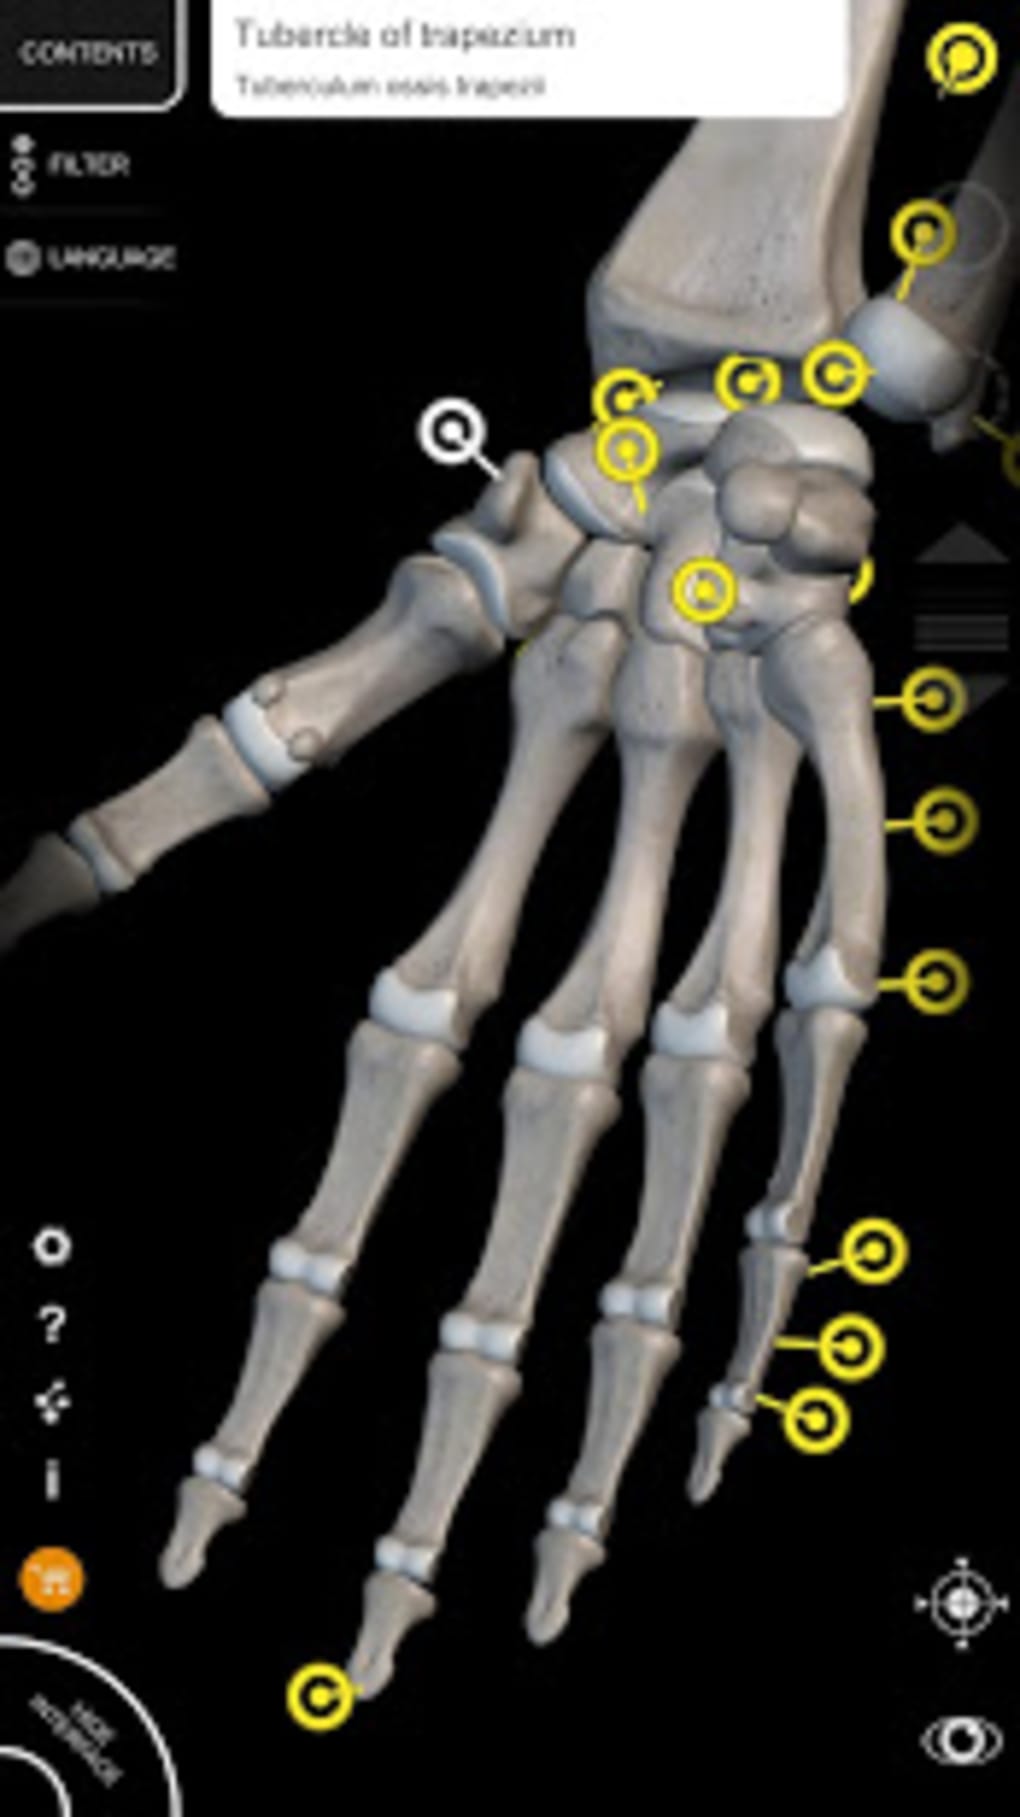

The app is based on the 3D model of the human body which is built with skeleton, muscles, bones, organs, and tissues. The anatomical models you will see in this app are the Respiratory System, Lymphatic system, Digestive System, Cardiovascular system, Eye and ear, and more.This app allows you to view the anatomy from a variety of angles, which makes it easy to study and understand.